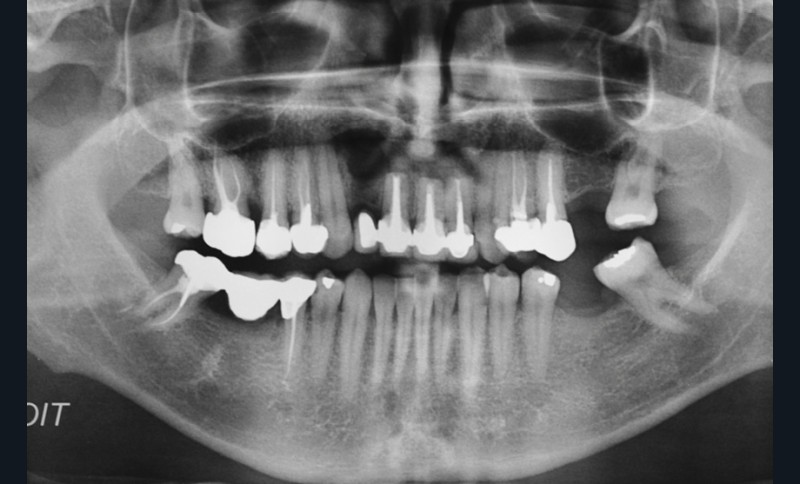

L’examen endobuccal montre deux fistules en regard des apex de 12 et 21 (fig. 1). Nous notons la présence d’une classe III squelettique, d’une occlusion inversée du côté droit (fig. 2) et des édentements non compensés au niveau de 26 et 36. L’orthopantomogramme révèle la présence d’une volumineuse lésion kystique qui s’étend de la 12 à la 22 (fig. 3).